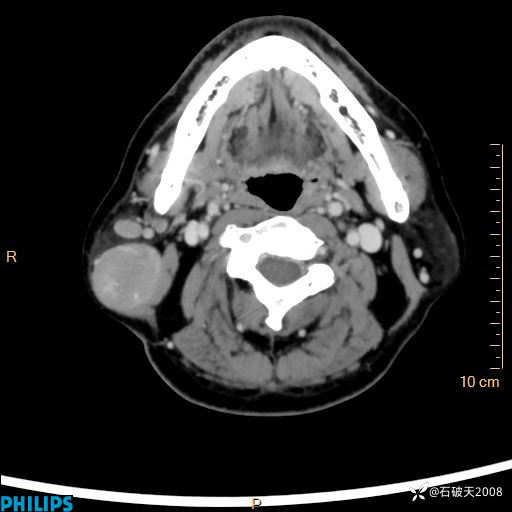

动脉期